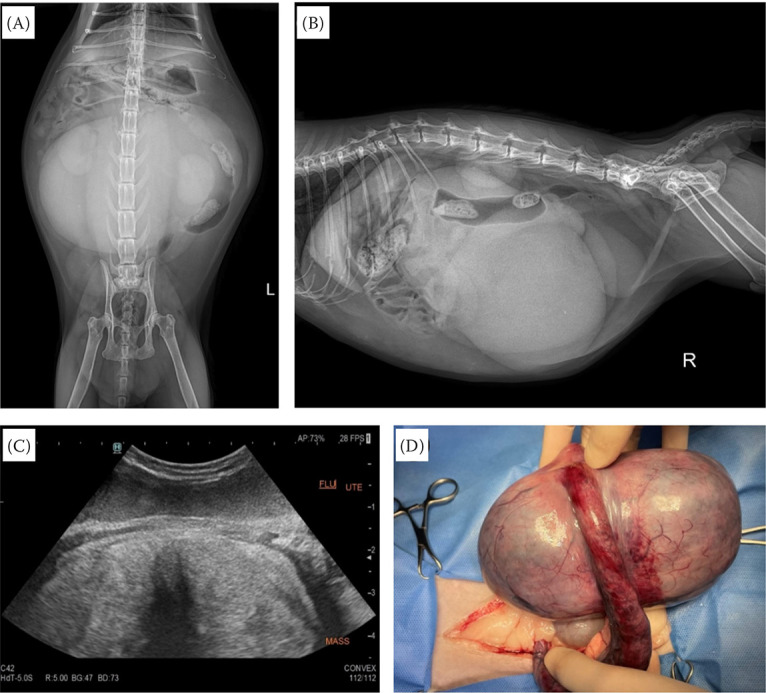

血管肌成纤维细胞瘤(AMFB)在人类和家畜中很少报道,特别是在女性生殖道中。这种无痛性肿瘤的特征是梭形或卵形肿瘤细胞增生,具有肌成纤维细胞分化,常聚集在薄壁血管周围。本报告首次报道了猫AMFB病例。术前腹部x线检查显示子宫增大伴卵巢背外侧移位,经腹超声检查显示子宫增大伴弥漫性低回声区。切除的子宫质地坚硬,呈灰褐色。显微镜检查显示分化良好的肿瘤梭形细胞在含有大量血管的丰富纤维间质背景下增生。未见粘液样变性和血管外渗。肿瘤细胞弥漫性α-SMA和vimentin免疫阳性,局灶性desmin免疫阳性(在血管周围)。AMFB在兽医学中是罕见的,本病例中观察到的猫子宫AMFB此前未见报道。虽然以前的报道是一种安全的良性肿瘤,但在没有正确诊断的情况下,对小动物进行大型AMFB的外科手术可能会危及生命。

Angiomyofibroblastoma (AMFB) is rarely reported in humans as well as domestic animals, especially in the female genital tract. This painless tumour is characterised by the proliferation of spindle or ovoid tumour cells with myofibroblastic differentiation, which often cluster around thin-walled blood vessels. This report presents a case of feline AMFB for the first time. Preoperative abdominal radiography demonstrated an enlarged uterus with the dorsolateral displacement of the ovaries, and transabdominal ultrasonography showed an enlarged uterus with diffuse hypoechoic areas. The resected uterus showed a firm texture with a grey to brownish colour. A microscopic examination revealed proliferation of well-differentiated neoplastic spindle cells on a background of abundant fibrous stroma containing numerous blood vessels. Myxoid degeneration and vascular extravasation were not observed. The neoplastic cells were diffusely immunopositive for α-SMA and vimentin and focally positive for desmin (in the perivascular areas). AMFB is rare in veterinary medicine and the feline uterine AMFB observed in the present case had not been previously reported. Although previously reported as a safe, benign tumour, a surgical procedure of a large AMFB in small animals without proper diagnosis may become life-threatening.